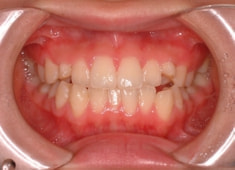

治療前